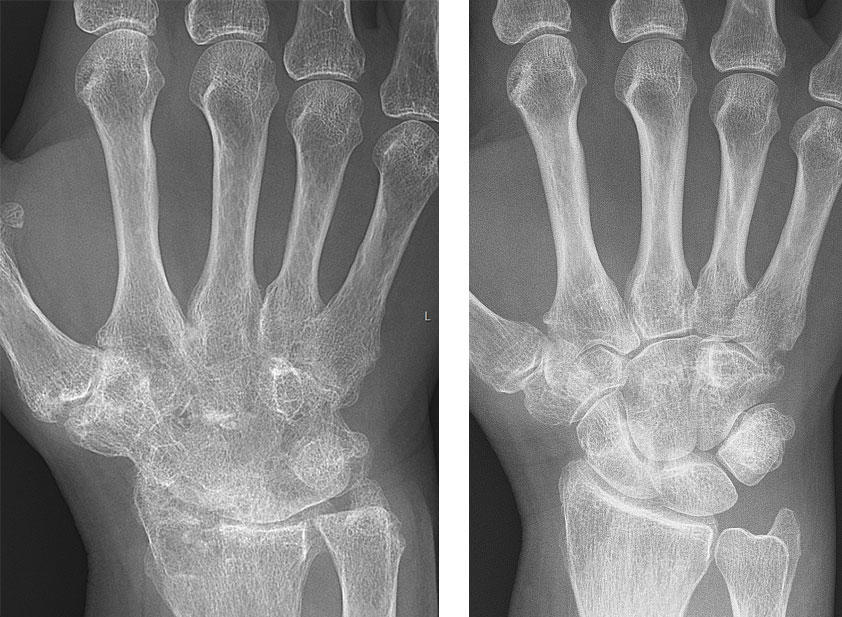

Radiografías de antes y después de la mano de una mujer con artritis reumatoide.

Imágenes radiográficas de la mano de una mujer con artritis reumatoide (izquierda) y ocho años después (derecha).

Fuente: Mikael Häggström, Creative Commons